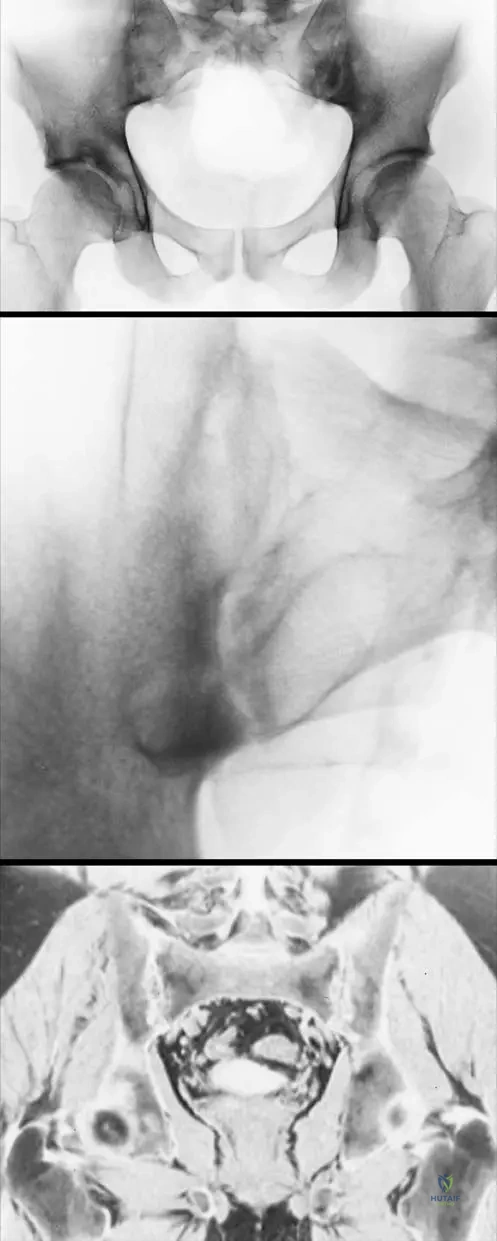

A 30-year-old male presents with chronic low back pain for 5 months. He notes the pain is worse in the morning and improves after he exercises. Physical examination shows limited lumbar spine movement. Radiographs of the pelvis reveal bilateral grade 3 sacroileitis.

Rationale: The Modified New York criteria for the diagnosis of AS include: (1) Low-back pain of more than 3 months’ duration/improved by exercise and not relieved by rest, (2) Limitation of movement of lumbar spine in sagittal and frontal planes, (3) Chest expansion decreased relative to normal values for age and sex, and (4) Bilateral sacroileitis, grade 2–4, or unilateral sacroileitis, grade 3–4. Unilateral sacroileitis, grade 1, is not a diagnostic criterion; it must be grade 3-4 for unilateral involvement. Options A, B, C, and E are all correct criteria.

A 32-year-old male presents with chronic low back pain. Radiographs of the pelvis are obtained.

Rationale: The Modified New York criteria for the diagnosis of AS specify "Bilateral sacroileitis, grade 2–4, or unilateral sacroileitis, grade 3–4." The image (Fig. 3.31a) shows bilateral grade 2-3 sacroileitis, which falls within the 2-4 range. Grade 1 (A) is typically considered too mild for a definitive bilateral diagnosis according to these criteria. Grade 0 (C) indicates no sacroileitis, and Grade 5 (D) is not a standard grading in this context.

A 25-year-old male presents with persistent low back pain. Radiographs of the pelvis are obtained, revealing bilateral grade 2–3 sacroileitis with sclerosis and erosions. Which of the following imaging modalities is most sensitive for detecting early sacroileitis, particularly before changes are evident on plain radiographs?

Rationale: While plain radiographs can show sacroileitis (as seen in Fig. 3.31a, b), MRI (Fig. 3.31c) is generally considered the most sensitive imaging modality for detecting early inflammatory changes in the sacroiliac joints, such as bone marrow edema, before structural changes like erosions and sclerosis become apparent on plain radiographs or CT. CT is good for bony detail but less sensitive for early inflammation than MRI. Bone scintigraphy is less specific, and ultrasound is not typically used for sacroiliac joint assessment.